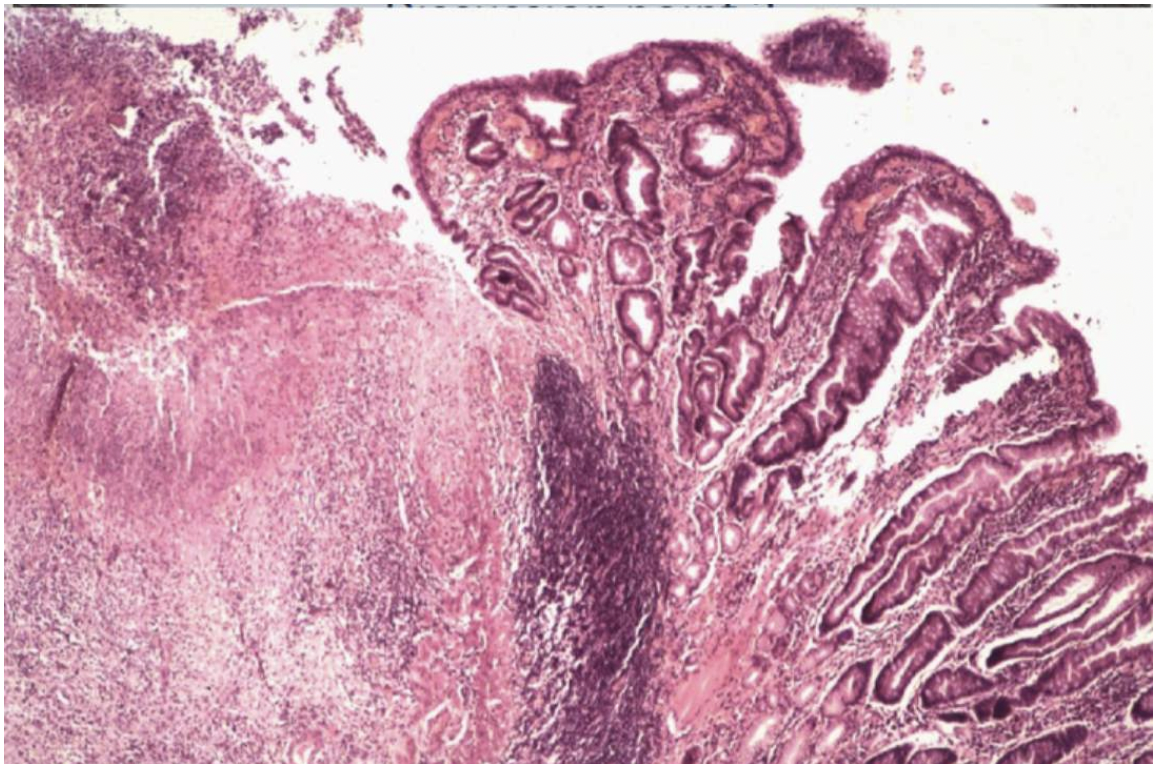

Describe what you can see in the histological images- where in the lesion does this tissue section come from?

Loss of glandular tissue on LHS

Inflammation causes hyperplastic inflammation to local tissues

What can you see in this image?

Looks like a ruptured artery-which may explain vomit

Completely ulcerated mucosa

Loss of muscularis layer